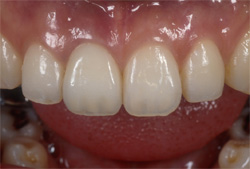

| インプラントの上のクラウンにより、あなたの咀嚼機能と自然な風貌が回復するでしょう。 |

| 失った部分にインプラントを1本埋入します。従来は健全な両隣の歯を削ってブリッジを用いて治療していましたが、インプラントを用いると健全な歯を削ることなく治療を行うことが出来ます。 |